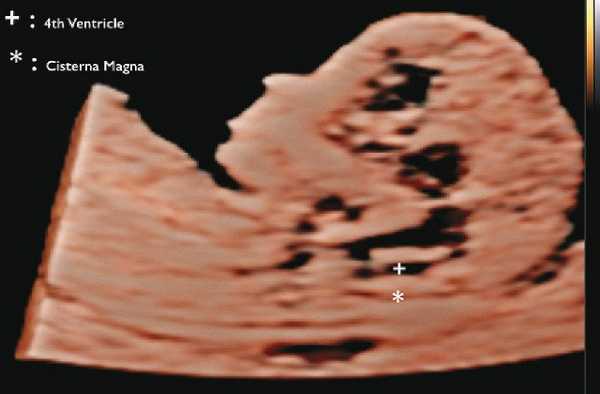

Расщепление позвоночника (spina bifida)

В прошлом лечащие врачи и врачи ультразвуковой диагностики проводили ультразвуковой скрининг для выявления дефектов нервной трубки, главным образом открытого расщепления позвоночника (spina bifida), во II триместре. В последние годы предложены ранние ультразвуковые маркеры на 11-14-й неделе беременности (внутричерепное пространство, использование БПР и соотношения БПР/ПРЖ (поперечный размер живота)), которые позволяют выявить у некоторых плодов высокий риск открытого расщепления позвоночника (рис. 7) 12.

Рис. 7. Внутричерепное пространство при ультразвуковом скрининге по поводу открытого расщепления позвоночника.